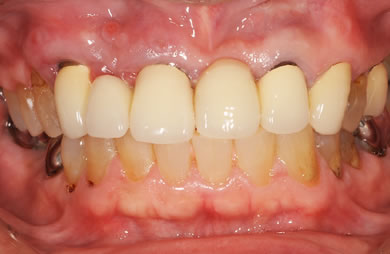

治療後

• 治療後